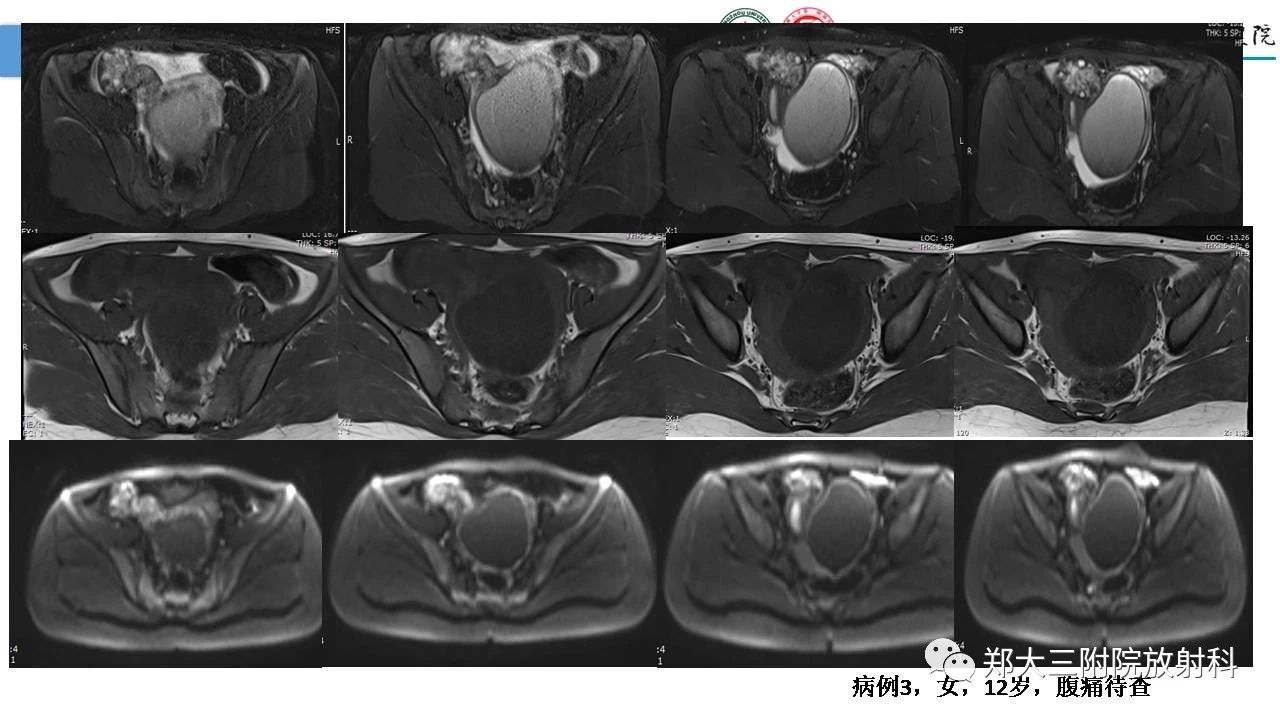

女性附件扭转的影像诊断